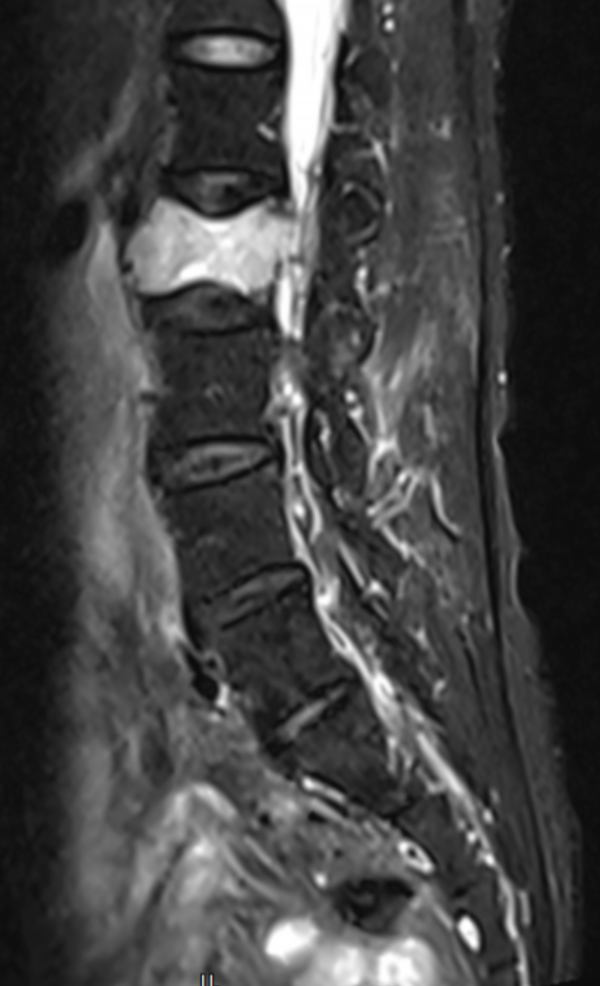

△ 術(shù)前MRI:腰2椎體骨質(zhì)破壞,考慮腫瘤性病變。